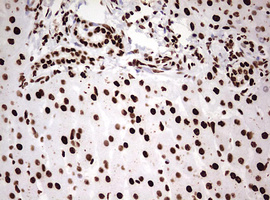

Immunohistochemical staining of paraffin-embedded Adenocarcinoma of Human endometrium tissue using anti-HNRNPM mouse monoclonal antibody. (Heat-induced epitope retrieval by 10mM citric buffer, pH6.0, 120°C for 3min, M06017-2)